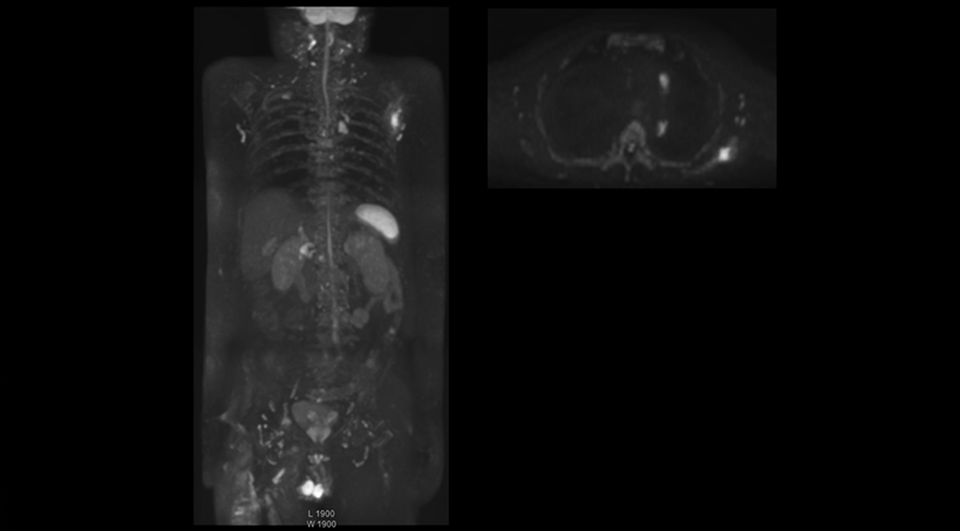

“mDIXON FFE allows us to quickly get information we need to assess the presence of fat. That gives us more information when we need to diagnose bone lesions, and when we are asked to judge fat-containing lesions such as hepatocellular or renal carcinoma,” Dr. Nobusawa says. “The mDIXON fat images can help us to differentiate fatty bone marrow from bone lesions. This is especially useful in elderly people, who tend to have fattier bone marrow. The water images provide a high signal-to-noise ratio in the intestinal canal, which is valuable for visualizing lesions in the colon,” he says.

Kawasaki Sawai Hospital’s whole body protocol also includes an mDIXON FFE sequence. Because mDIXON provides images for four contrast types – water only, fat only, in-phase and out-of-phase – from a single acquisition, it is useful in many ways.

“In-phase and out-phase sagittal T1-weighted FFE images help us to visualize and further characterize bone lesions such as metastasis and bone-marrow hyperplasia that have high signal on DWI. These images are also used throughout radiotherapy, to monitor changes in the fatty bone marrow.”